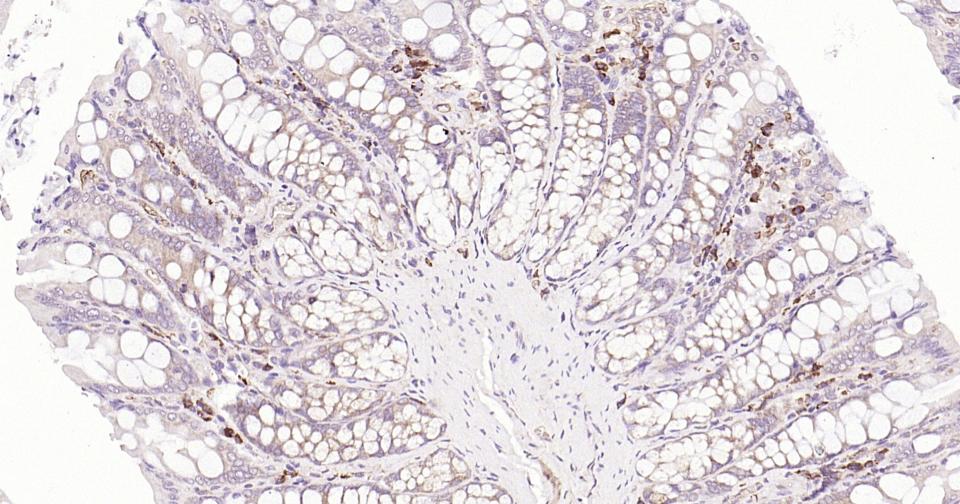

| 应用 | 已检合格种属 | 预测种属 | 推荐稀释比例 |

|---|---|---|---|

| IHC-P | Human, Mouse, Rat | 1:100-500 | |

| IHC-F | Human, Mouse, Rat | 1:100-500 | |

| IF | Human, Mouse, Rat | 1:100-500 |

交叉反应: Human, Mouse, Rat